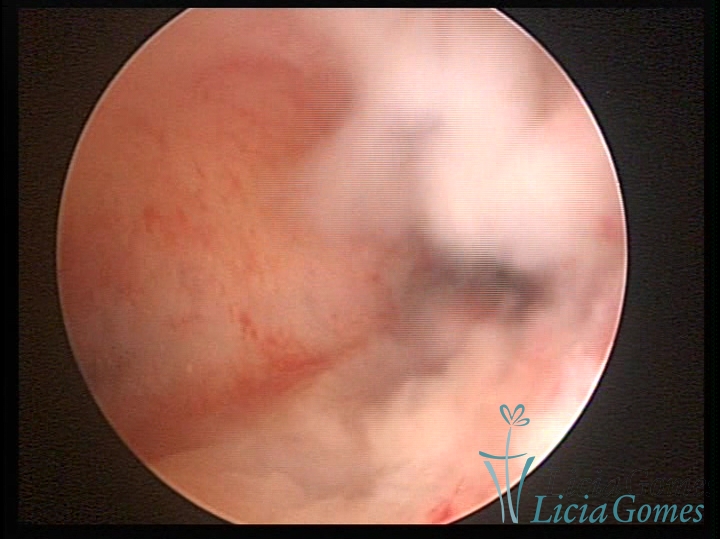

Septate uterus

It probably occurs by the lack of resorption on the middle line, in the merge of Müllerian ducts. The uterus is divided by a partial or total septum which is viewed as a crossbar, not covered by endometrium, which not bleeds when sectioned.

Complete septum when it occupies the whole extension of the cavity, dividing it into two hemicavities.

When this septum occupies only a part of the extension of the uterine cavity, it is considered as incomplete.